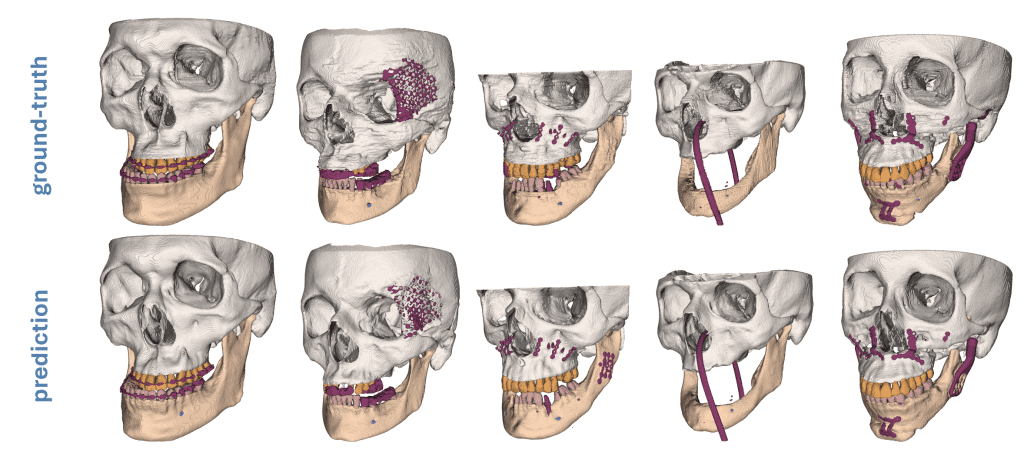

Deep Learning basierte Segmentierung von Unterkiefer, Gesichtsschädel, Zähnen, Kieferkanal und Metallstrukturen als Grundlage für patient*innenspezifisches Implantatdesign.